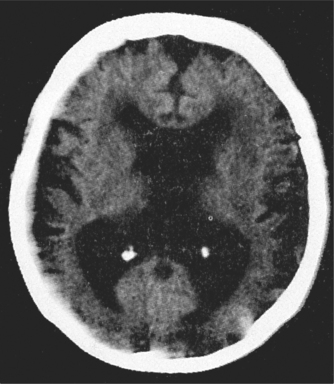

There are over 200 other causes of dementia but these are uncommon. A few are occasionally at least partially reversible (e.g. hypothyroidism, vitamin B12 deficiency, syphilis) and explain why investigations for these are performed. Normal pressure hydrocephalus (characterised by dementia, urinary incontinence and gait disturbance) is also potentially reversible, although many neurosurgeons are reluctant to perform the required shunt, as results are often disappointing.

Routine blood tests and neuroimaging should be performed as shown in Box 57.3—mainly to rule out potentially reversible causes of dementia and comorbidities. Increasingly, specialists are ordering tests to ‘rule in’ a diagnosis of dementia and to characterise the type.

The MRI of the brain is moving towards this identification of dementia—for instance, hippocampal atrophy is seen in AD, and frontal atrophy in FTD. The PET scan is only available in a few centres but can be most useful. The FDG PET shows a characteristic pattern in AD (bilateral temporoparietal hypometabolism with sparing of occipital metabolism), whereas sparing of the posterior cingulate metabolism is very much against a diagnosis of AD. In DLB, occipital metabolism is reduced and in FTD frontal and temporal metabolism is down, with characteristic patterns in the language variants. Another PET technique available in even fewer centres is amyloid imaging using PIB or other agents. Absence of amyloid excludes AD, and its presence excludes FTD. Amyloid is frequently found in DLB and vascular dementia. Combining both PET techniques achieves very high diagnostic accuracy.